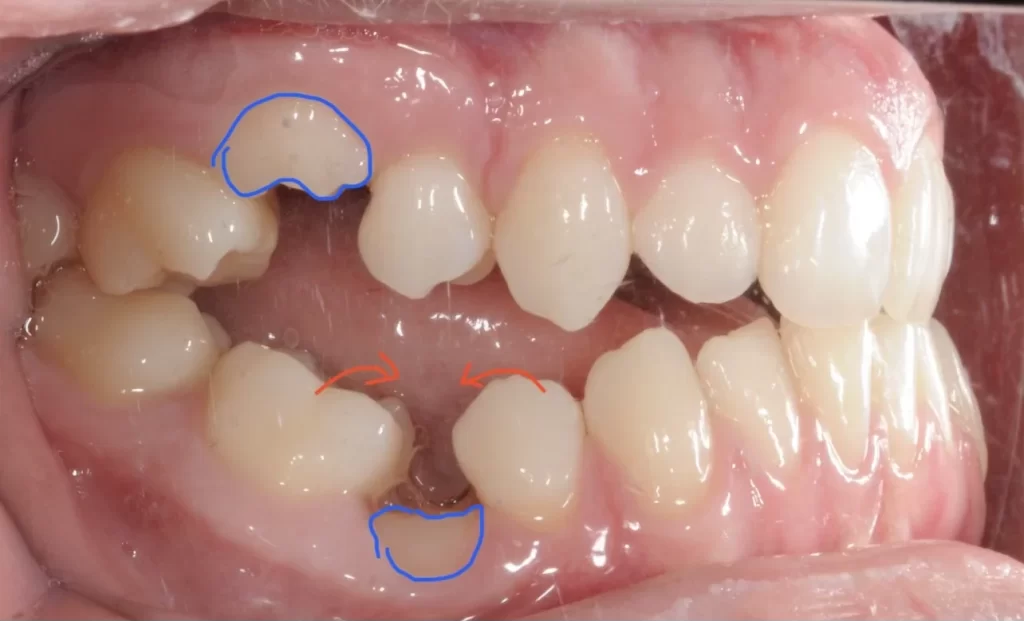

Migrarea dinților vecini – dinții rămași tind să se deplaseze spre spațiul liber, ducând la probleme de aliniere și mușcătură incorectă.